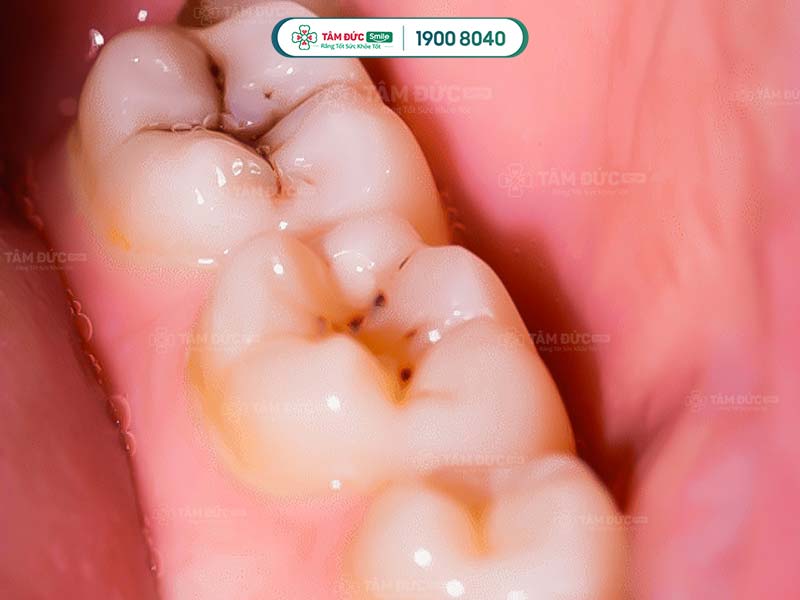

1.1. Bề mặt răng có các đốm nâu đen

Đây là dấu hiệu điển hình nhất khi răng khôn bị sâu. Các đốm nâu đen này xuất hiện do vi khuẩn sâu răng tấn công và ăn mòn men răng, gây sâu răng.

2.2. Sâu răng khôn do hình dạng răng khác biệt

Răng khôn có hình thể và bề mặt lớn hơn các răng khác. Mặt nhai của răng khôn có nhiều rãnh nhỏ, là nơi lý tưởng để vi khuẩn tích tụ và phát triển.